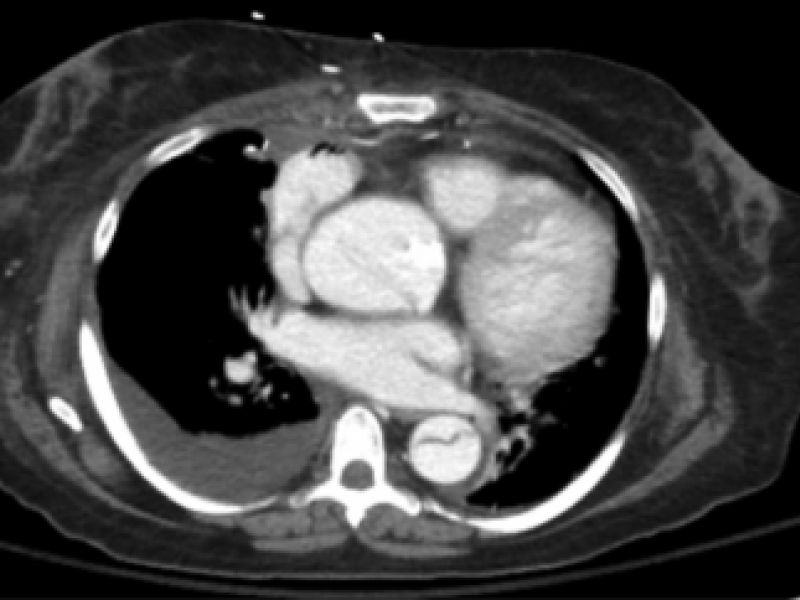

A 43 yo F presents to the ED with RLQ abdominal pain x 3